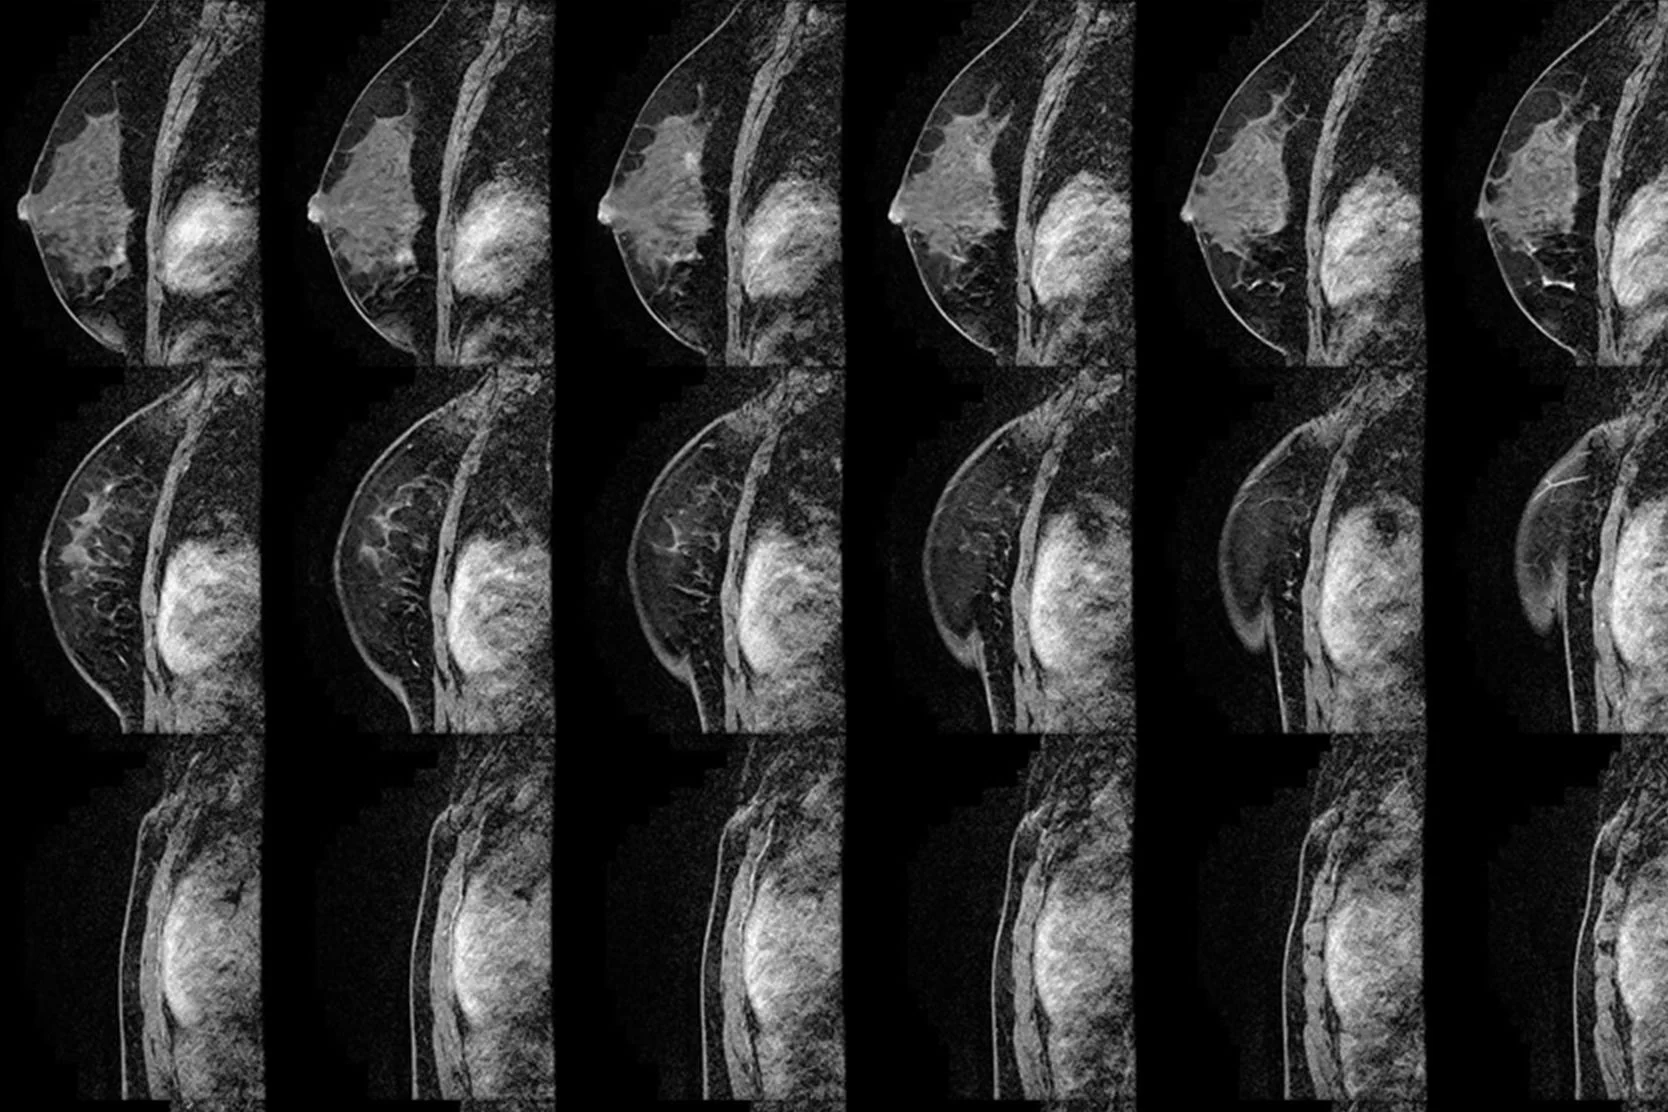

- Breast magnetic resonance imaging (MRI). This type of MRI scan can reveal abnormalities that aren't visible through mammography or ultrasound. Each scan produces hundreds of images.

The American Cancer Society recommends that certain women with an especially high risk of developing breast cancer have an MRI scan along with their yearly mammogram. A breast MRI is noninvasive, with no radiation exposure. But breast MRI is an evolving technology and shouldn't replace standard screening and diagnostic procedures, such as in-clinic exams during a regular checkup, self-exams, mammograms and biopsies.